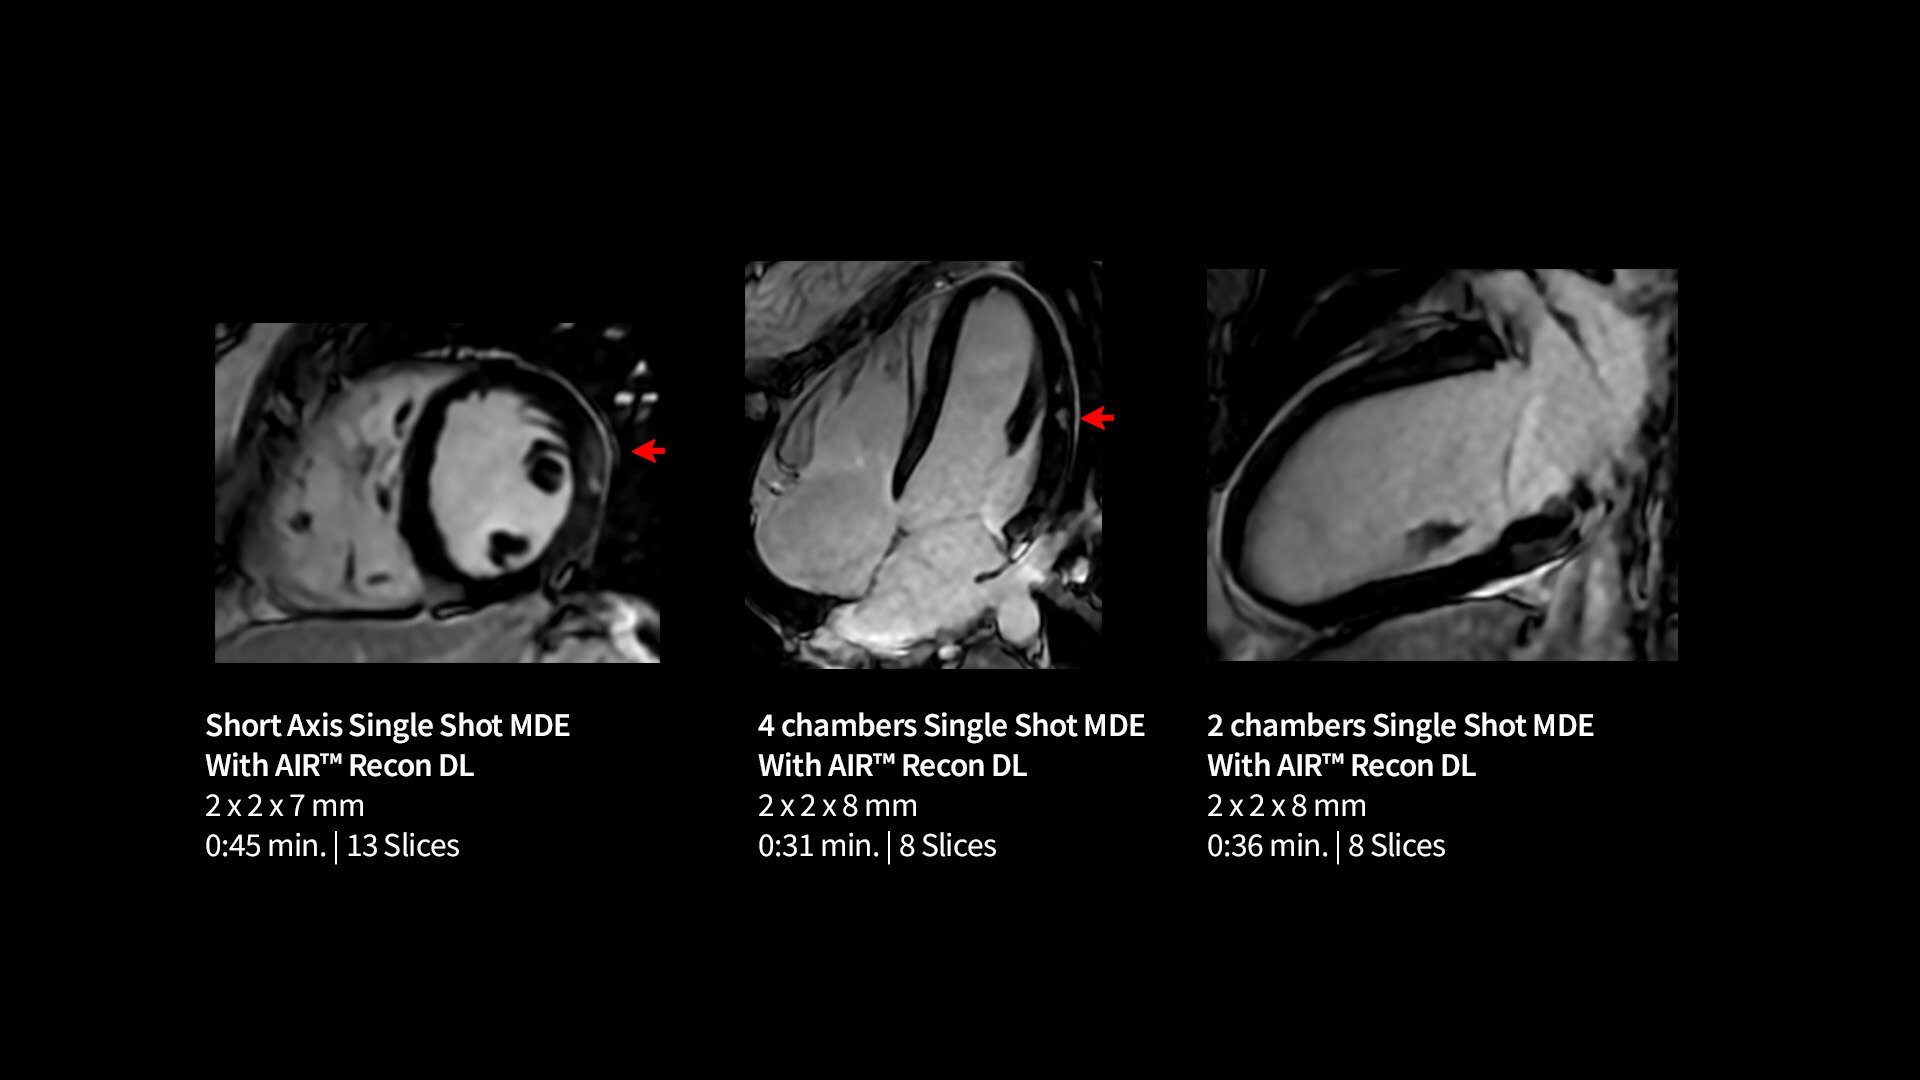

Every step of our cardiac MR assessment is compatible with our pioneering deep-learning algorithms, including: morphology, function, perfusion, mapping and myocardial viability with late enhancement.

Your teams can capture clarity with AIR™ Recon DL, a revolutionary technique to boost image quality, providing accurate anatomic information and advanced soft tissue contrast. It’s already transformed the lives of millions of patients worldwide since 2021. Thanks to Sonic DL™ they can also now assess cardiac viability faster than ever before, with as little as 15 to 20 minutes per scan.*†